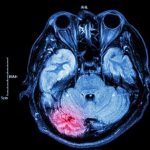

• differenze nel cervello: alcune persone con DOC hanno aree cerebrali con attività inusuale o con bassi livelli di una sostanza chimica chiamata serotonina